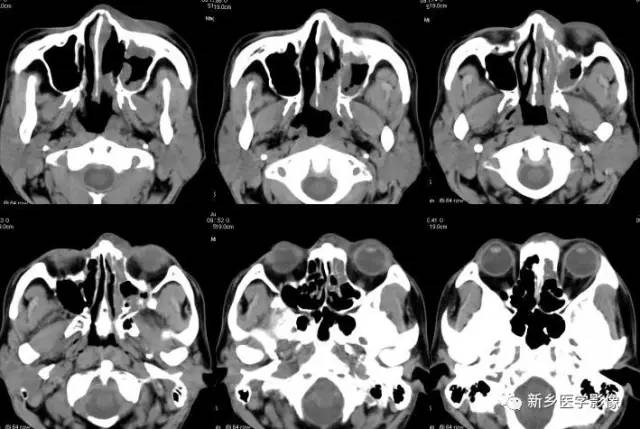

鼻腔及鼻窦恶性肿瘤

鼻腔,鼻窦良,恶性肿瘤的ctmr诊断(一) | 影像天地

鼻部肿瘤,您想到了吗?